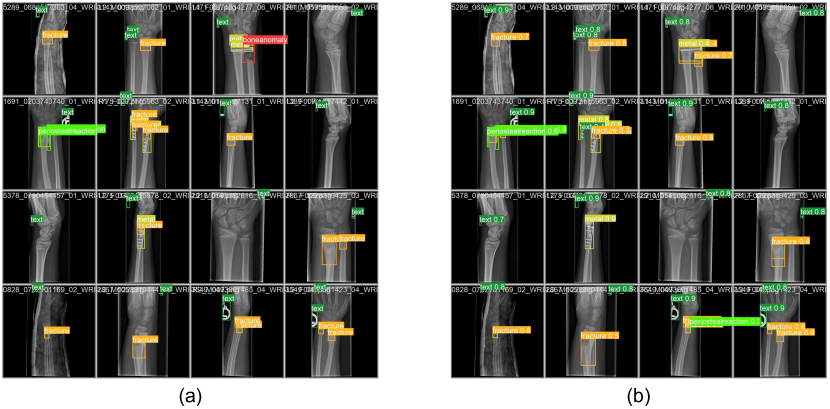

This paper aims to design a pediatric wrist fracture detection application, so we use our model for fracture detection. Figure 6 shows the results of manual annotation by the radiologist and the results predicted using our model. These results demonstrate that our model has a good ability to detect fractures in single fracture cases, but metal puncture and dense multiple fracture situations badly affects the accuracy of prediction.